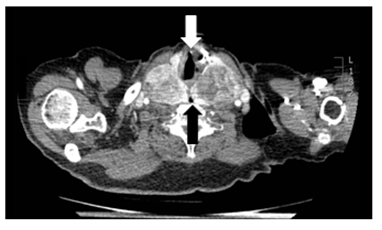

Laboratory testing reveals a TSH 1.14μU/mL (0,35-5,28). Chest radiography does not show tracheal deviation. Gastroscopy does not present esophageal alterations. Cervicothoracic CT shows a multinodular goiter with posteromedial spreading of both lobes that compress faryngoesophageal union and proximal esophagus (black arrows in Figures 1 and Figure 2). Also, larynx and trachea are displaced forward (white arrows in Figures 1 and Figure 3). Right thyroid lobe measures 5,2x4,9x7,8cm. Left thyroid lobe measures 5,7x4,9x8,8cm. Patient is dismissed for surgery due to high anesthetic risk. Currently, patient tolerates turmix diet and fluids with thickeners. Although isolated dysphagia is an uncommon symptom in compressive goiters, whose main manifestation is dyspnea, it is important to rule out an enlargement of the thyroid gland as a cause of dysphagia even in the absence of dyspnea, dysphonia or visible goiter.

Figure 2